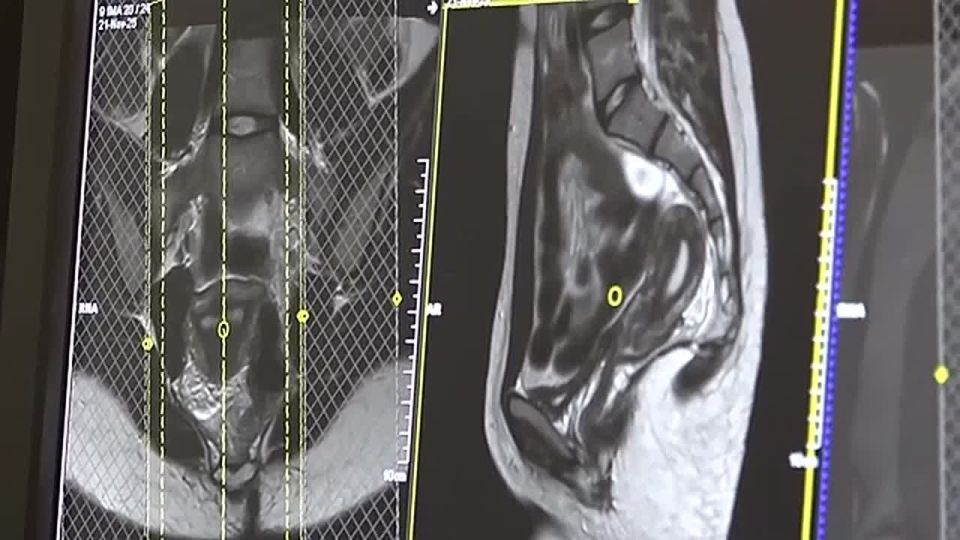

Экскурсию для учеников школы космонавтики провели в Красноярском краевом клиническом центре охраны материнства и детства. Ребятам показали все потаённые уголки медучреждения, рассказали о принципах работы и сложных случаях. Вместе со школьниками...